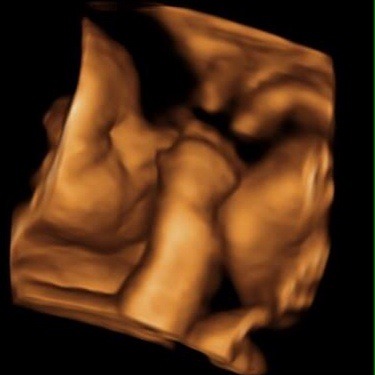

Went for a 4d scan today and got some fantastic piccies of my baby girl .... Heres sone for those not on fb.

June 2015 - bumps ahoy!

Ahh jazzy they are lovely...... Grin

Thanks chook, we were amazed at the images we got, never had 1 before and would totally recommend it.

She did lots of baby checks aswell and gave us a weight and length estimate.